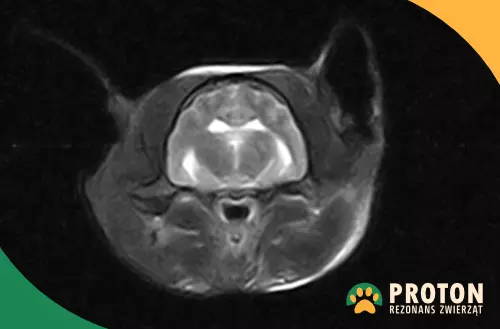

Obraz RM mózgu kota

Rezonans mózgu kota